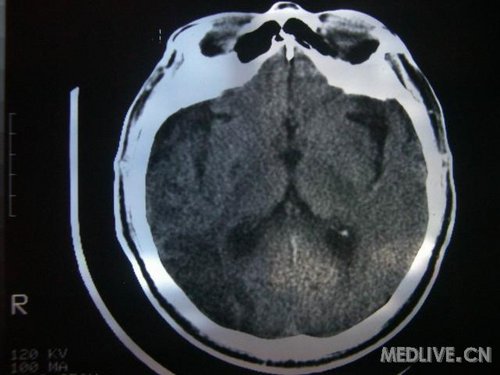

病人男性 73岁 市民 以“幻听、幻视两天,言语含糊、精神错乱一天”入院。

两天前无诱因出现幻听、幻视,描素眼前有彩色的圆圈,听见有人说话(但说什么不详),一天前出现胡言乱语,言语含糊,精神错乱,问话不答,行走略有不稳,来我院就诊,门诊头CT检查:(下面有片)入院后查体不合作,表情淡漠,问话不答,大致检查了一下,颅神经未见明显异常,颈软,右手活动似忽略差。其他检查不配合。脑电图:广泛轻-中度异常。

既往史:半年前曾患“右侧脑梗塞”但无明显后遗症,生活能自理,无高血压、糖尿病、心脏病史。

先传半年前的片子: